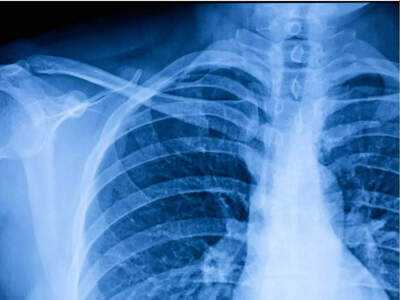

Dr. Sudhir Kumar, a neurologist trained at Christian Medical College (CMC), Vellore, and currently practicing at Apollo Hospitals, Hyderabad, recently emphasized the need for caution when it comes to routine chest X-rays. Sharing his professional opinion on X (formerly Twitter), Dr. Kumar stated that most individuals do not require annual chest X-rays unless there is a strong medical reason.

He explained that these scans are commonly included in annual “master health checkups” or pre-employment medical screenings, yet for healthy individuals with no symptoms, they rarely offer any significant benefit. According to Dr. Kumar, a yearly chest X-ray in such cases seldom identifies any major illness early, but it does expose the person to unnecessary radiation and may lead to additional, often avoidable, tests.

Dr. Kumar advised that chest X-rays should only be considered when there are valid medical indicators—such as persistent cough, unexplained fever, significant weight loss, a history of smoking, a risk of tuberculosis, or occupational exposure to harmful substances. He further asserted that the practice of conducting these X-rays as a routine part of health checkups or job screenings lacks evidence-based justification.

The doctor urged people to embrace what he called “smart health,” meaning a mindful and informed approach to diagnostic testing—choosing tests wisely rather than opting for more tests without a clear clinical need.